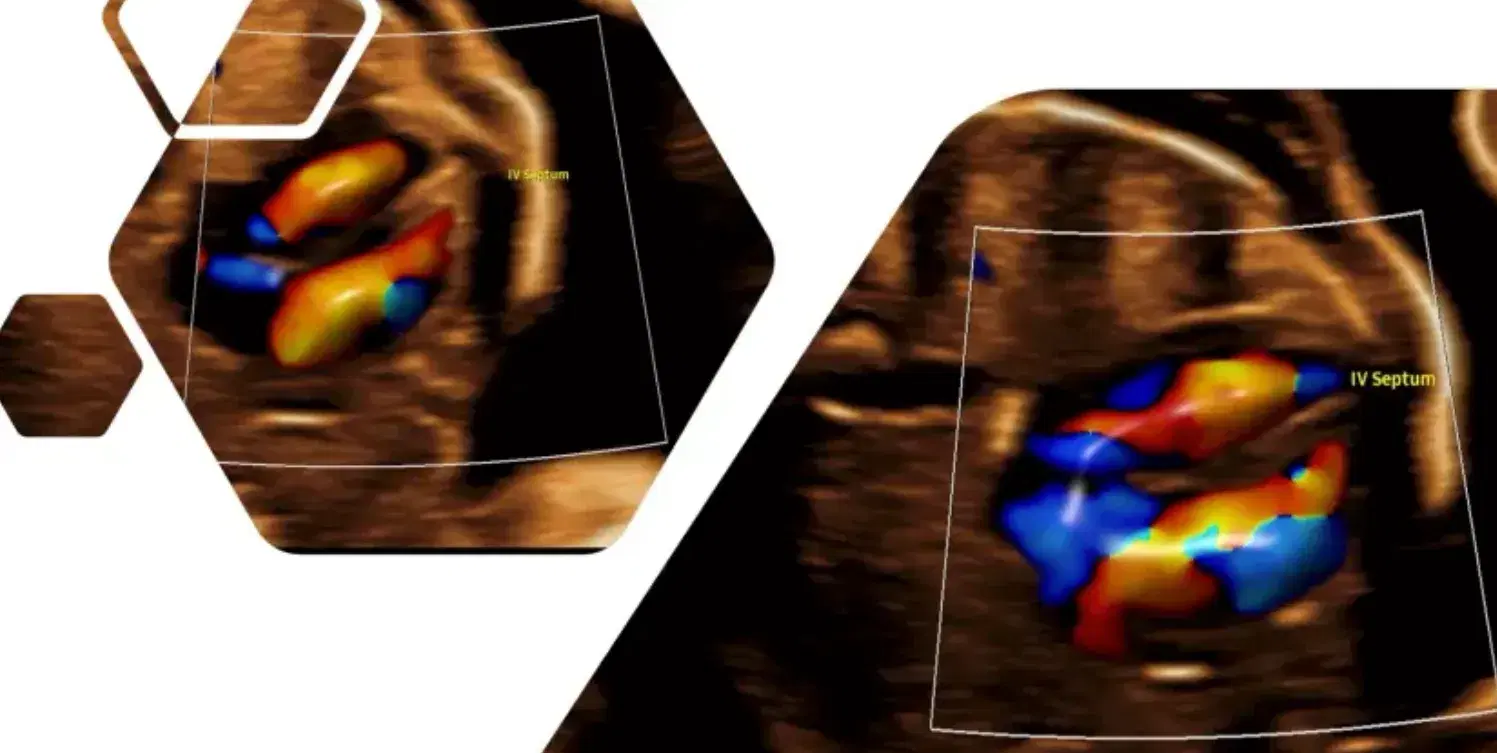

Use imaging effectively: Master ultrasound features, like echogenic masses or cysts, and use color Doppler to rule out mimics like bronchopulmonary sequestration.